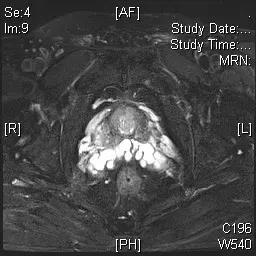

患者杨某某,60岁,因排尿困难入院,前列腺特异性抗原:TPSA(总前列腺特异性抗原)38.930ng/ml;FPSA(游离前列腺特异性抗原)5.720 ng/ml;FPSA/TPSA 14.69%。前列腺MR增强检查提示:前列腺周围带左侧份异常信号灶,考虑前列腺癌。

图一 前列腺磁共振

9月10日,傅强教授团队为患者实施了磁共振(MRI)-超声(US)影像融合靶向前列腺穿刺活检术。根据术前前列腺MR影像和TRUS(经直肠超声)图像,将两者图像融合,标记可疑病灶,进行靶向穿刺。